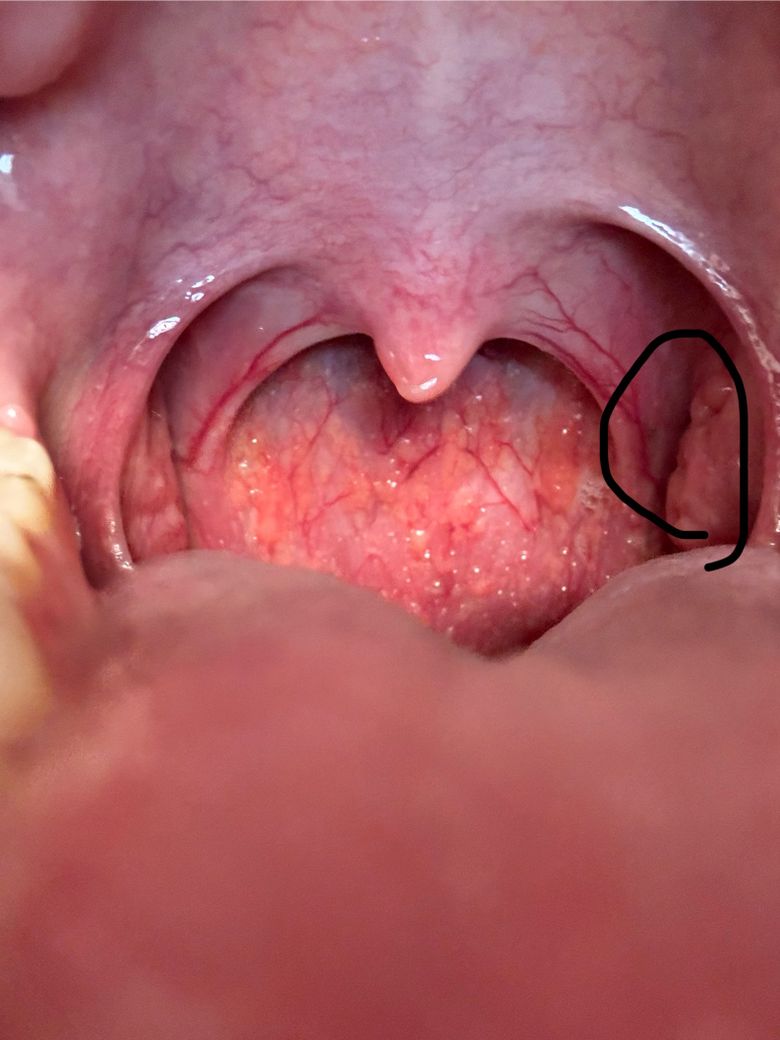

한동안 역류성 식도염이 있었는데 그 이후로 인후두쪽에 이물감이나 막히는 느낌이 있었습니다. 편도도 좀 부은 느낌이 들어 입 내부를 보니 한쪽 편도만 부풀어 있었고 종기같이 볼록 나와있는 부분도 있었습니다. 편도가 저렇게 붓기도 하나요? 아직까지 큰 불편감은 없는 수준이긴 합니다.

올려주신 사진에서 편도가 잘 나오진 않았으나 비대를 의심할 정도로 커져 보이진 않습니다.

인후두쪽에 이물감이나 막히는 느낌이 지속된다면 이비인후과 진찰을 받아보시기 바랍니다.